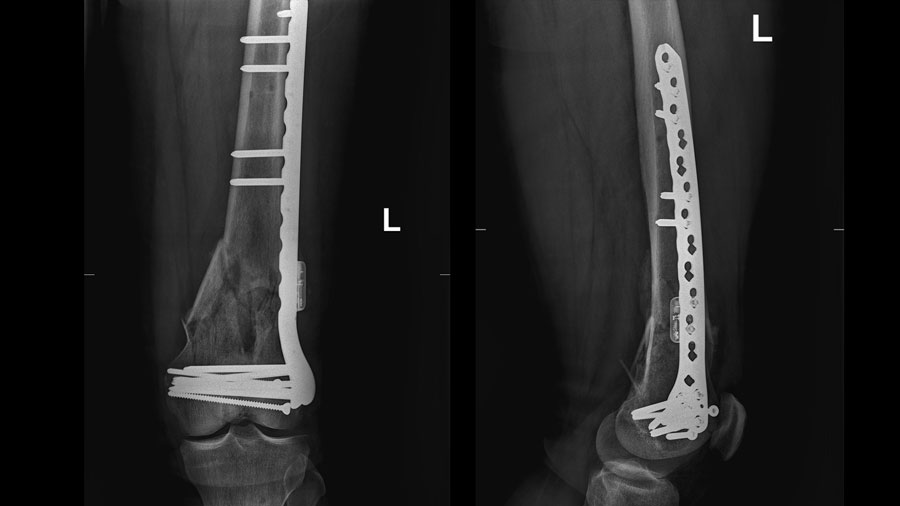

Patient convalescing following first-in-human AO Fracture Monitor application

Sixty-five years after the AO was established to champion revolutionary internal fixation techniques that continue to achieve unprecedented results in fracture healing, its legacy of improving patient outcomes continues with the first-in-human application of the AO Fracture Monitor developed by the AO Research Institute Davos (ARI) with the AO’s innovation funding. In an important step toward regulatory approval, the safety of this implantable telemetric sensor system is now being validated in a multicenter clinical trial at four hospitals in Germany.

The system, which represents an innovative approach to individualizing patient rehabilitation, arose from talks between former ARI Focus Area Leader Concept Development Dr. Markus Windolf and AO founding father and longtime ARI Director Prof Stephan Perren. After many design iterations and fine-tuning, and eventually formal product development, a new kind of telemetric system was created, and the development team is happy to now have an active implantable device ready for clinical application. The current clinical study got underway in autumn this year with so far two patients enrolled. Over the next months, a total of 37 patients will be recruited at the participating hospitals BG Klinik Tübingen, Universitätsklinikum des Saarlandes, Universitätsklinikum Ulm, and Universitätsklinikum Münster.

“It was an incredible experience to be able to observe the first surgery and actually see how the AO Fracture Monitor was implanted in a patient after so many years of development,” she recalled. The current study is expected to conclude in spring 2025 and provide the missing data for the subsequent conformity assessment by the notified body for market approval in Europe. “We anticipate a CE mark by the end of 2025 and availability for larger clinical studies by early 2026.”

“The AO Fracture Monitor is revolutionary in that it represents a step away from relying on traditional modalities like x-rays and toward a much more patient specific and accurate ways of monitoring bone healing,” he said. “The AO is helping make this project possible with not only funding but expertise at every step of development. To make a great idea a reality, you need strong partners, and the AO—with the AO Innovation Translation Center, including AO's innovation funding and Clinical Evidence teams, all the way to ARI—is truly a full-service resource.”